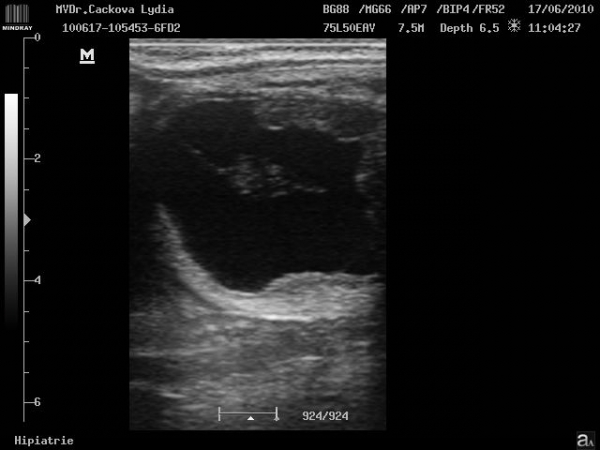

ultrasonografické vyšetření klisny

Preovulační folikul

embryo kolem 21.dne

Embryo 31. den